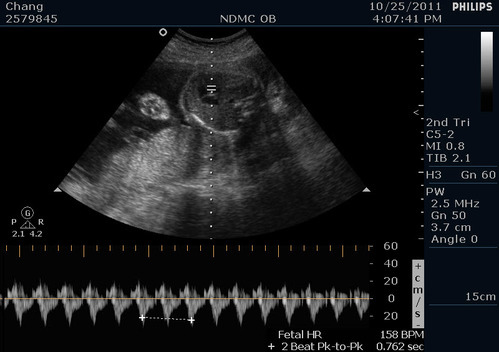

心跳每分鐘158下~而且很規則沒有心律不整